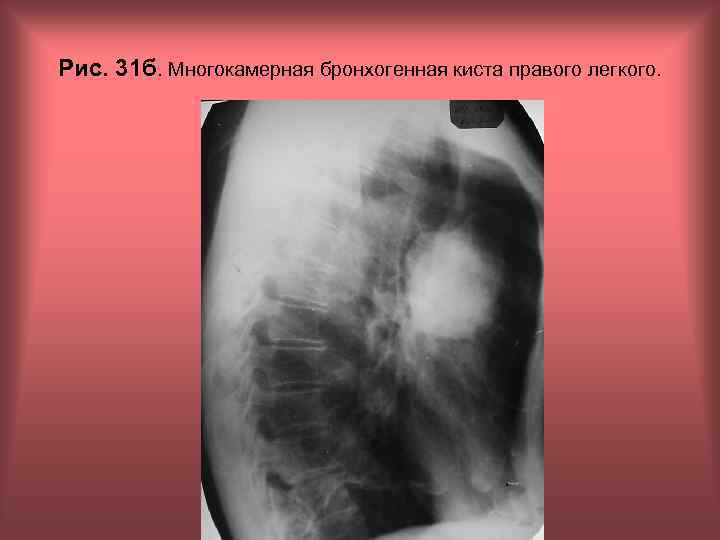

Рис. 31 б. Многокамерная бронхогенная киста правого легкого. Н. С. Воротынцева, С. С. Гольев Рентгенопульмонология